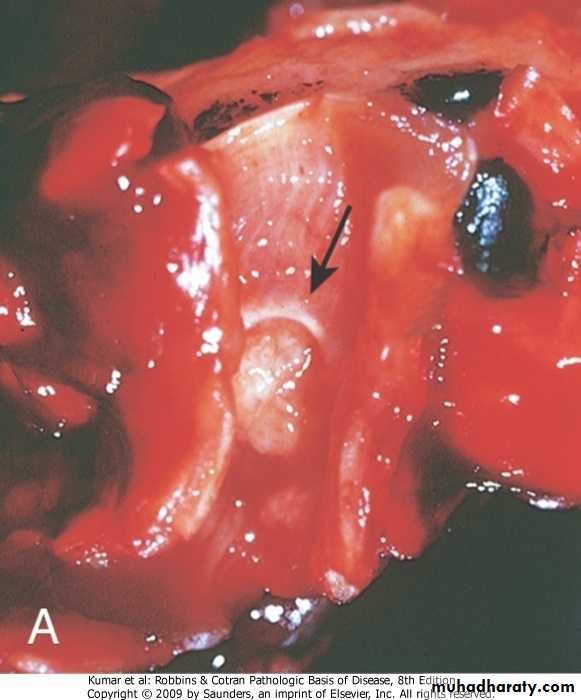

Advanced silicosis, fibrotic nodule, arrow